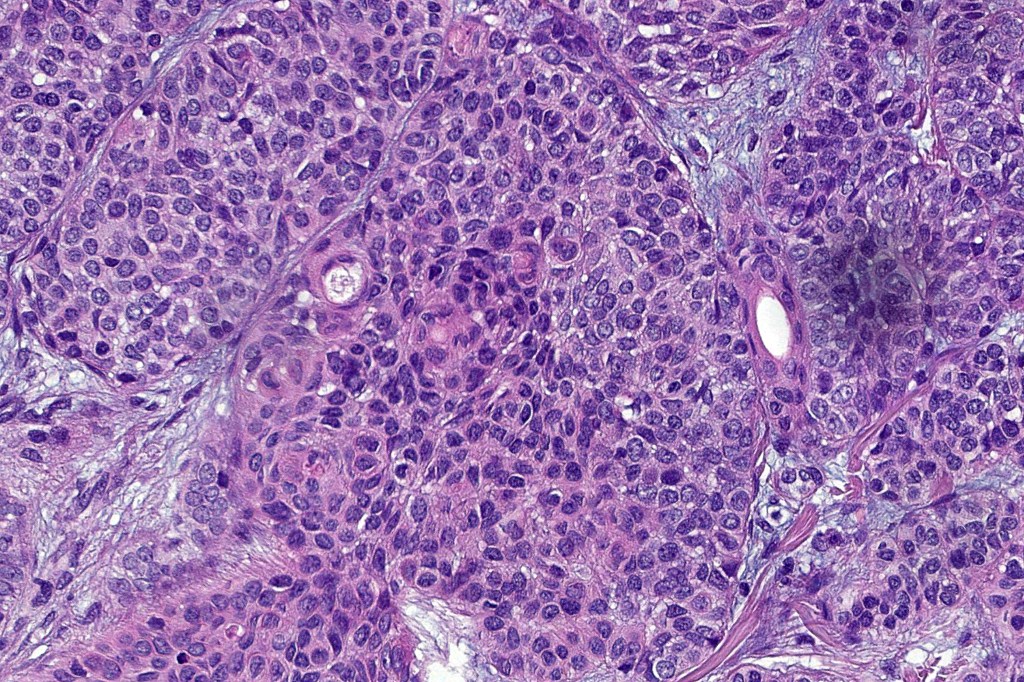

•High grade trichoblastic carcinoma is characterized by high grade carcinoma arising in a trichoblastoma. TP53 &PIK3CA mutations have been documented

•Trichoblastic sarcoma is characterized by readily recognizable trichoblastoma associated with a high grade sarcomatous element